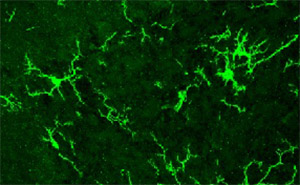

Para entender el mecanismo involucrado, los investigadores estudiaron en los roedores el efecto de la exposición prenatal a VPA sobre la activación de las células de la glía: aquellas que se encargan de dar sostén a las neuronas y defienden al cerebro del daño. Los resultados fueron sorprendentes: observaron signos de inflamación sólo en la crías hembras, las “protegidas”, pero no en los machos.

“La glía podría mediar mecanismos compensatorios que eviten que se afecten las neuronas que regulan la sociabilidad”, interpretó Depino.